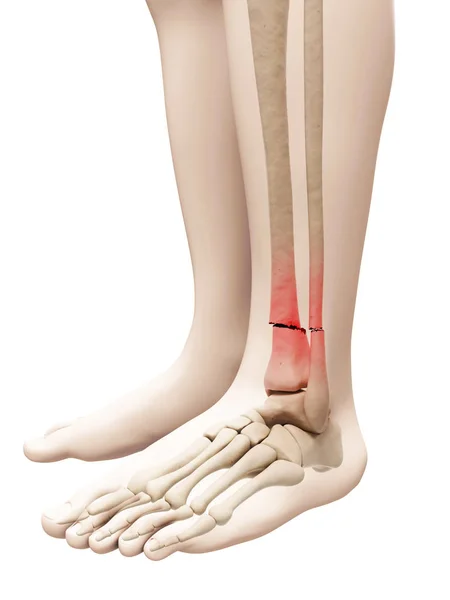

A broken bone is never easy, but some fractures are more complicated than others. A complex fracture refers to a severe break where the bone is shattered into multiple fragments, involves the joints, does not heal properly, or is accompanied by infection or deformity. Unlike simple fractures that usually heal with a plaster cast, complex fractures require specialised orthopaedic care and advanced surgical techniques.

A complex fracture is defined as a bone break that is severe, unstable, or involves complications. These fractures may include:

• Intra-articular fractures: fracture extends into the joint surface.

• Visible deformity or abnormal limb shape.

• Open wounds with exposed bone (in open fractures).